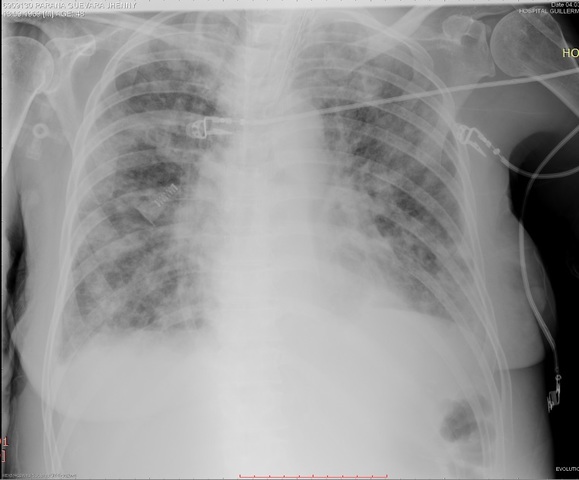

SE RETIRA VASOPRESORES

SE CONTINUA CON VANCOMICINA EN Rp PESE A INDICACIÓN DE INFECTOLOGIA

ANEMIA SEVERA Hb 6,4, SE TRANSFUNDEN 2 PG

ACTUALIZA ANALITICA, RX TORAX